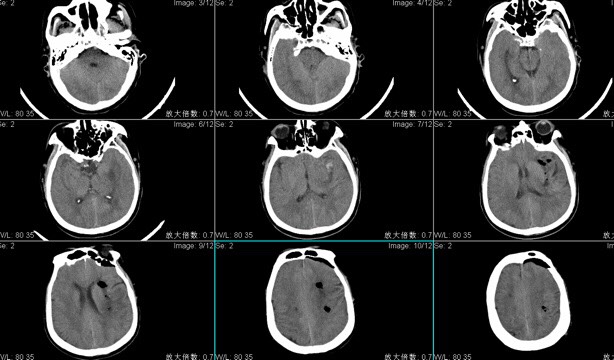

患者陈XX,男性,59岁,主因“突发右侧肢体无力伴言语含糊1小时余”入院;头CT检查显示左侧基底节区脑出血多田公式计算出血量约80ml;手术入路:神经内镜辅助经左额脑出血清除术。

术后复查头CT显示血肿清除良好,神经内镜辅助脑出血手术时间短,损伤性小恢复快